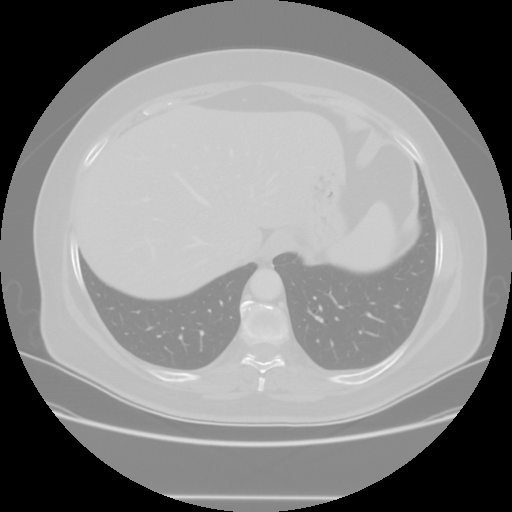

Generated VENOUS CT scan (A→B translation)

No window - Raw intensity values

Lung window (WL -600, WW 1500 β†’ Low βˆ’1350, High +150)

Mediastinum window (WL 40, WW 400 β†’ Low βˆ’160, High +240)